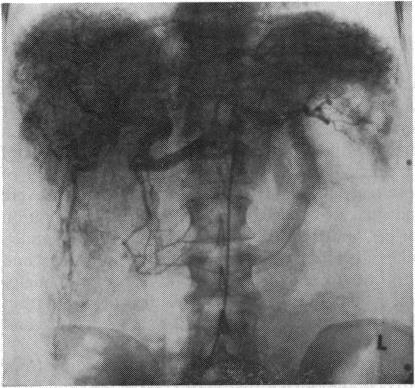

Hereditary haemorrhagic teleangiectasia (Rendu-Osler-Weber disease) is an inborn error of vascular structure with multiple manifestations. Its incidence is about 1-2:100 000 in the European population. The incidence of telangiectases and/or fistula formation was estimated to be 1 in 10 carriers of the Osler trait. The findings in the family reported herewith suggest a much higher incidence if angiography is more frequently performed. Apart from the skin and mucous membrane, teleangiectases and/or arteriovenous fistulas may be present in the lungs, intestinal tract, spleen, kidney, brain, and bones. The liver apparently is more involved than was orginally suspected. The vascular derangement includes teleangiectases, arteriovenous fistulas, and connective tissue formation with fibrosis and atypical cirrhosis. In intestinal bleeding laser coagulation seems to be very efficient. The pathogenesis of teleangiectases is not known but involves several factors such as special formation of venules, capillaries and arterioles, abnormal perivascular connective tissue and endothelial cells.

遗传性出血性毛细血管扩张症(伦迪-奥斯勒-韦伯病)是一种具有多种表现的先天性血管结构异常疾病。在欧洲人群中,其发病率约为1-2:100000。据估计,奥斯勒特征携带者中毛细血管扩张和/或瘘管形成的发生率为1/10。本文报道的该家族研究结果表明,如果更频繁地进行血管造影,发病率会高得多。除皮肤和黏膜外,肺部、肠道、脾脏、肾脏、大脑和骨骼中也可能存在毛细血管扩张和/或动静脉瘘。肝脏受累程度显然比最初怀疑的要高。血管紊乱包括毛细血管扩张、动静脉瘘以及伴有纤维化和非典型肝硬化的结缔组织形成。对于肠道出血,激光凝固似乎非常有效。毛细血管扩张的发病机制尚不清楚,但涉及多个因素,如小静脉、毛细血管和小动脉的特殊形成、血管周围结缔组织和内皮细胞异常。